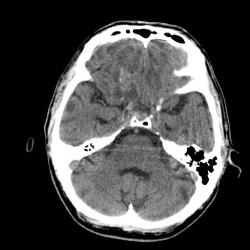

Мужчина 48 лет. Со слов родственников, почувствовал себя плохо и упал.

1-я серия -исследование сразу после травмы.